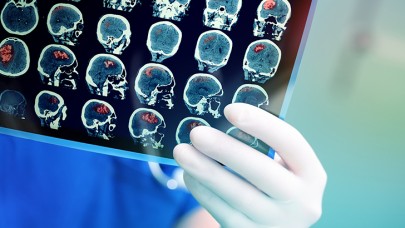

Migrenin beyindeki etkisi ilk kez görüntülendi